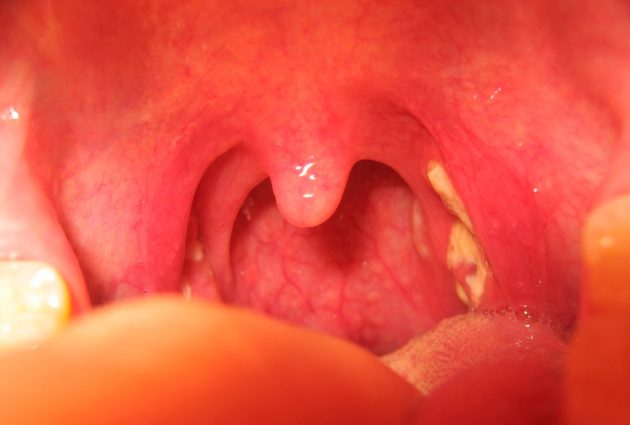

Это воспаление слизистой ротоглотки. Фарингит — одно из самых распространенных заболеваний в практике ЛОР-врача. Основной симптом — боль при глотании, даже при глотке без пищи, а также рыхлость, гиперемия и отечность задней стенки глотки. При катаральном фарингите отек симметричен, что можно легко проверить, взглянув в зеркало с открытым ртом.

Если боль локализуется с одной стороны, необходимо обратиться к отоларингологу. Асимметрия указывает на наличие очага воспаления, отличного от общего процесса, и может свидетельствовать о латерализации очага.

Глотка — подвижное образование с рыхлой подслизистой оболочкой, склонной к отеку. При простудах, переохлаждении или гриппе возникают различные симптомы — першение, щекотание, боль — но они обычно не имеют четкой локализации.

При осмотре наблюдается отечный и напряженный купол слизистой. Необходима срочная госпитализация в специализированное отделение для вскрытия абсцесса и назначения антибиотиков, что быстро улучшит состояние пациента.